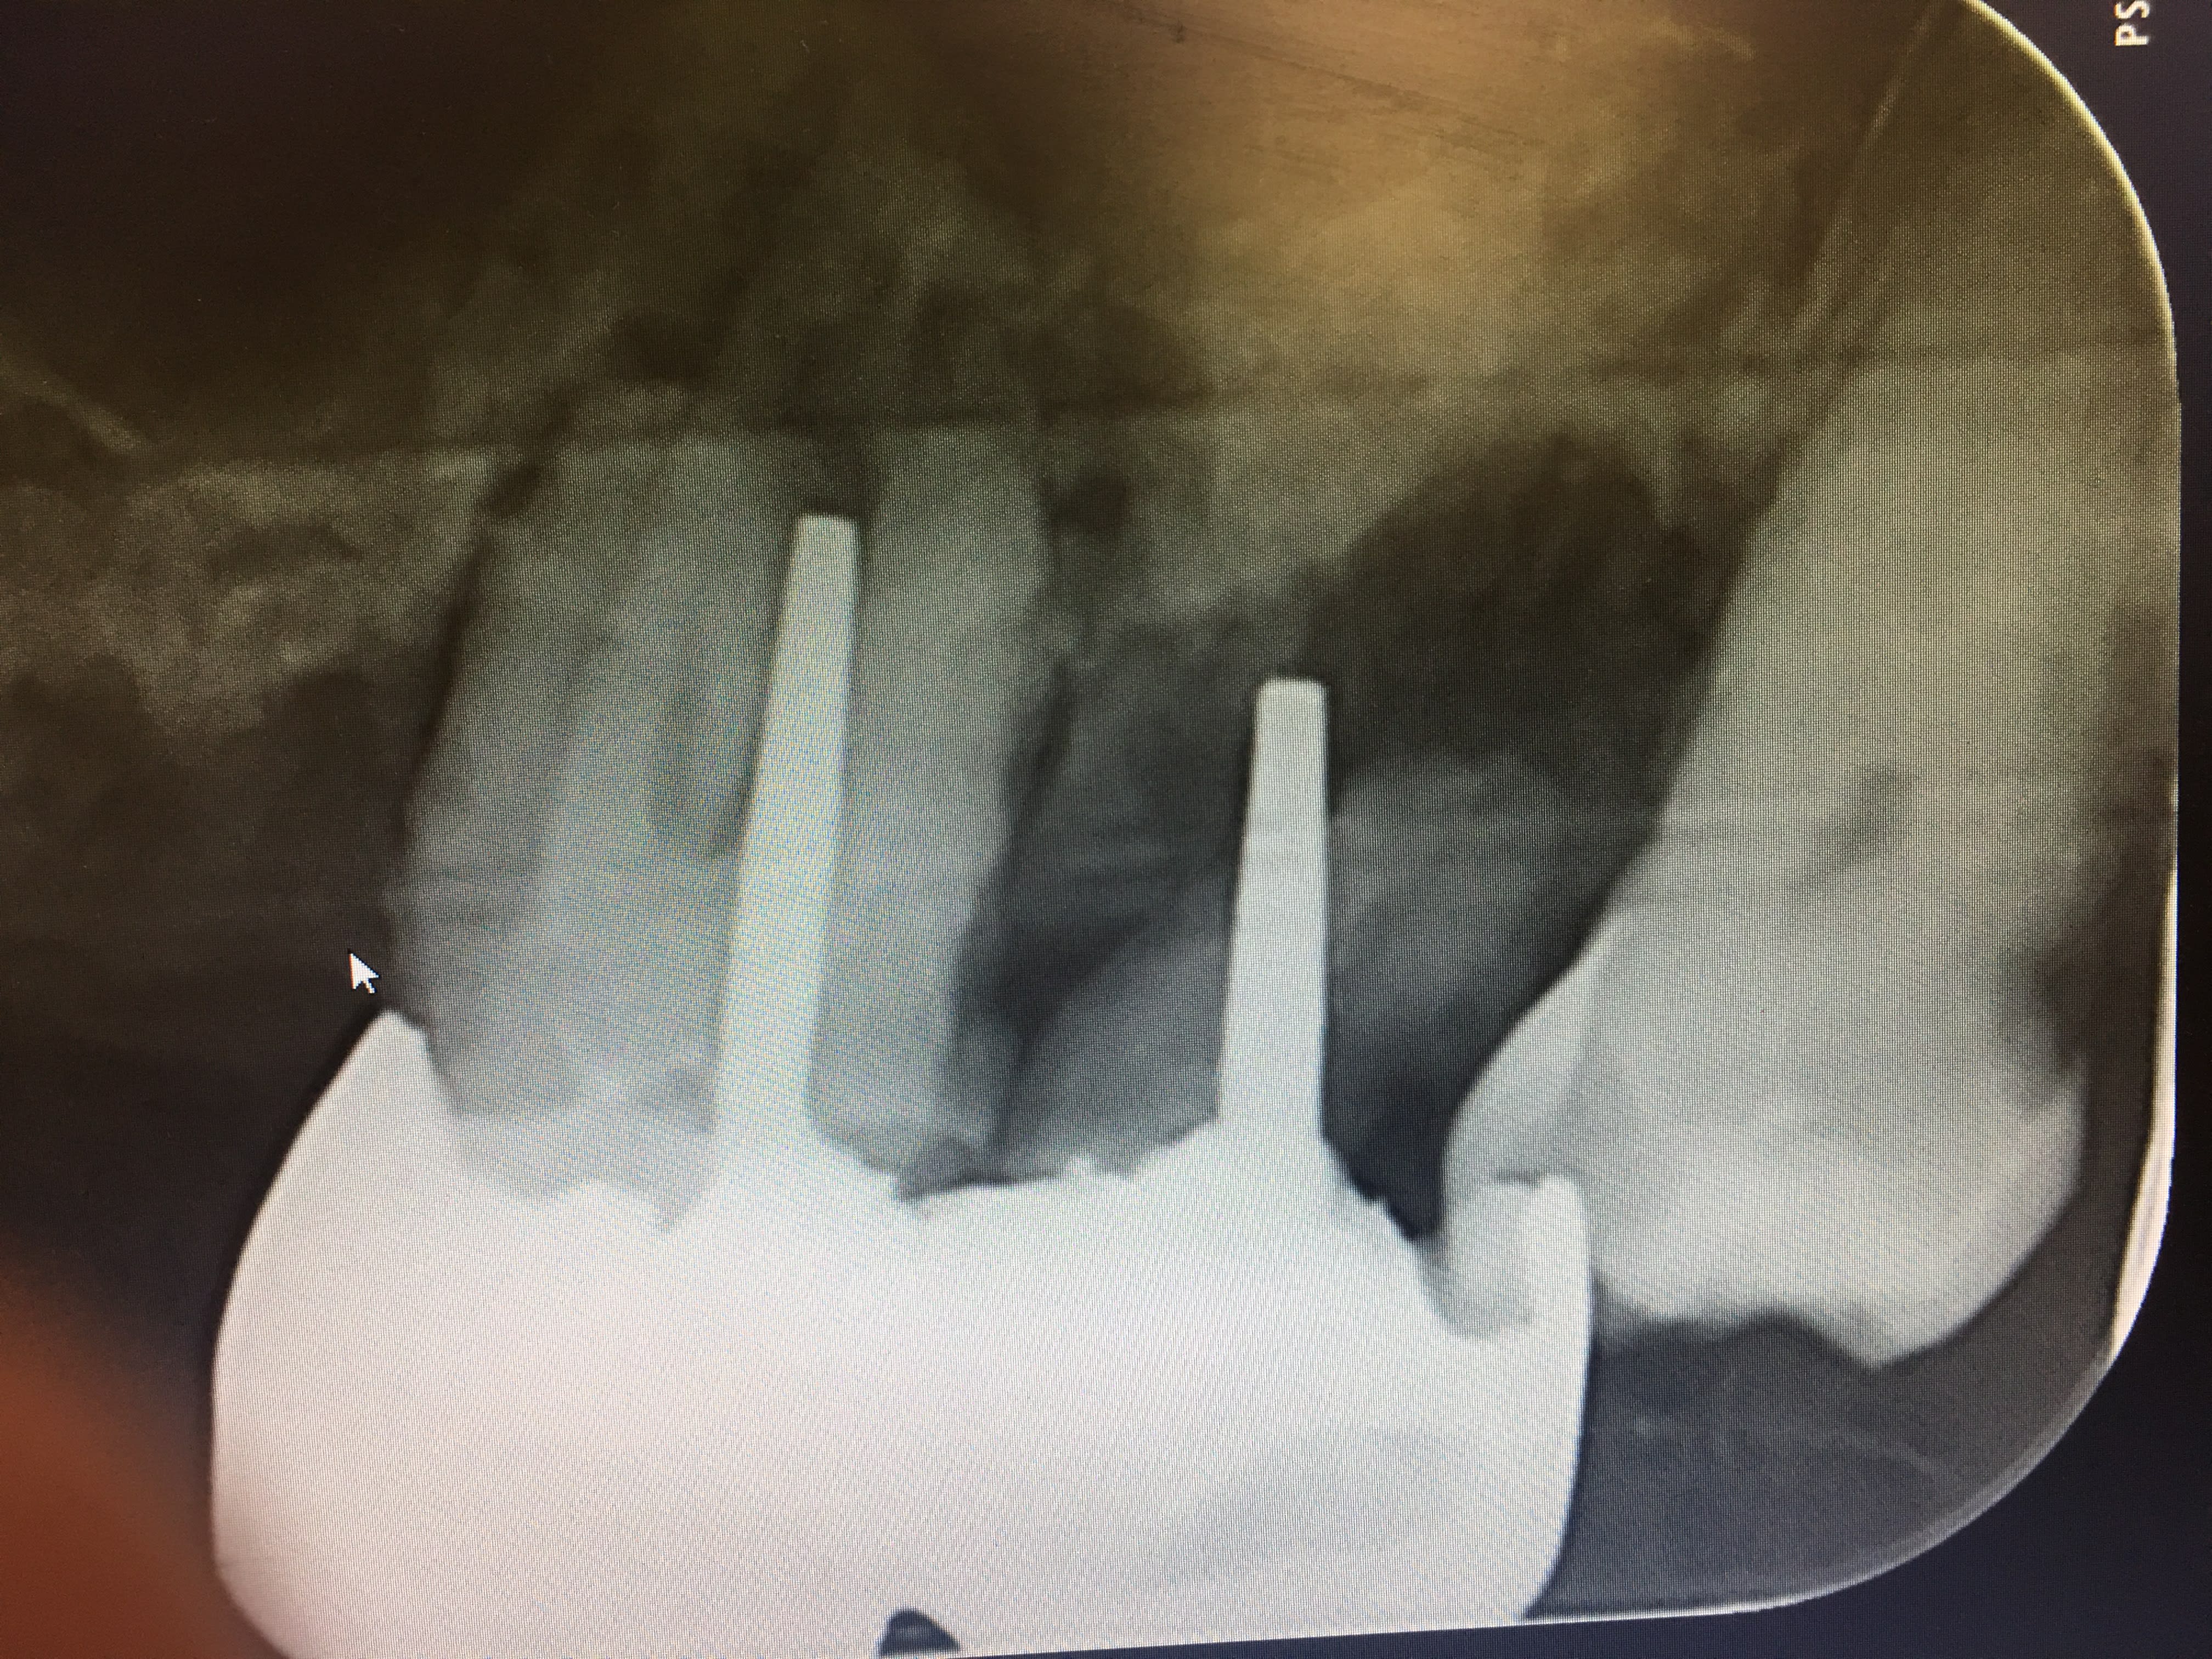

Tu tombes bien toi. Nouveau patient vu en urgence à la fac ou a été réalisée une ouverture de chambre légèrement "distalée" comme tu peux le constater. La douleur s'est amplifiée curieux non ? -)

Je fais quoi ? J'apporte ma modeste contribution à l'édifice qualité en incitant le patient à entamer une procédure contre la FAC ? -)

Ton comportement est inadmissible tu n'es pas juge et parti et ca va certainement te retomber sur la tronche un jour.

Tu me donnes combien sur 20 en endo "professeur" ? -)

Capture d écran 2017 05 06 13.32 - Eugenol